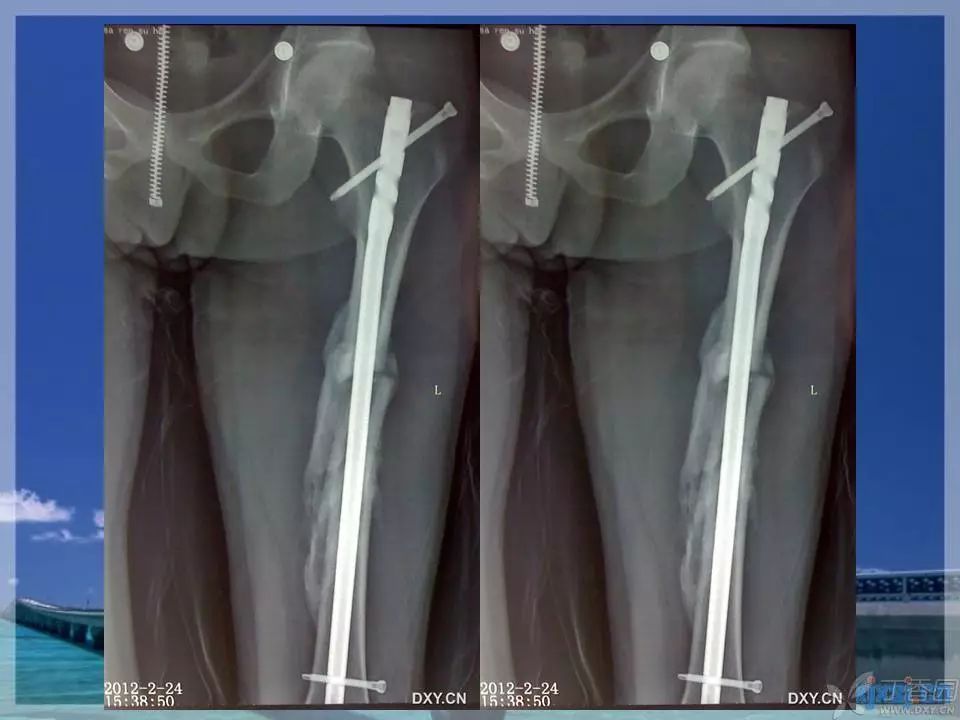

股骨干骨折是临床常见骨折之一,闭合复位髓内针固定治疗已成为首选。那么复位标准是怎样的?骨折块分离多少可以接受?钢丝可不可以用?不扩髓可以吗?相信看完下面这个课件你会有所收获~

1. ppt 中提到蝶形骨块移位大于 1cm 会影响股骨干骨折的愈合,这是一个台湾学者的观点,图中可以看见股骨内侧和后侧已经有骨痂生长,所以说 1cm 这个数据有待商榷。大于 1cm 的移位骨折愈合也不是什么问题。

5. 只有稳定 / 萎缩型才是实施动力化的适应症,而不稳定 / 萎缩型实施动力化后,并发症的发生率最高,应避免应用。对于肥大型,无论是否稳定,也不建议实施动力化,这是因为肥大型本身即是由于骨折端不稳所致,实施动力化后,无疑会使得这种不稳变得更加严重。